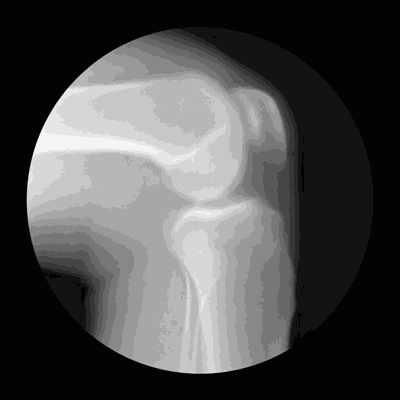

可能大家都会觉得,世界那么大,我想去看看!在此要提醒小伙伴们一句,爬山的前提是要保护好我们的膝关节,毕竟膝关节是消耗品,会越用越少,一旦磨损不能修复,只能更换。

如何预防膝关节老化、损伤?

1.要控制体重,避免膝关节负担过重,注意保护关节,避免关节受伤;

2.要注意腿部的保暖,避免腿部直接被冷风吹;

3.要进行合理的体育锻炼,科学运动。

久坐或久站的人,平日应当要注意多活动腿和腰部,以加强血液循环。值得注意的是,关节已有不适感的人群,不要选择“负重”的运动,如爬山、爬楼梯、蹲起等膝关节负重的运动,以避免或减少关节软骨的磨损。